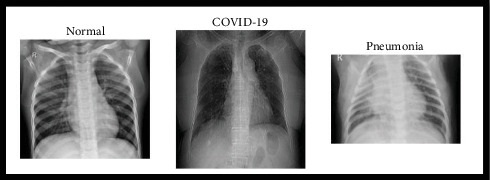

Lung diseases, including pneumonia and COVID-19, are prevalent globally, necessitating early diagnosis for effective treatment. Medical imaging is widely regarded as an effective method for detecting lung diseases. Numerous researchers have dedicated their efforts to developing advanced detection techniques, significantly contributing to the prevention and management of these conditions. Despite advancements in imaging diagnostic methods, chest radiographs remain pivotal due to their cost-effectiveness and rapid results. This study proposes an automated system for detecting multiple lung diseases in x-ray and CT scans using a customized convolutional neural network (CNN) alongside pretrained models and an image enhancement approach. The dataset used comprises 6400 images sourced from Kaggle, categorized into three classes: pneumonia, COVID-19, and normal. To address dataset imbalance, data augmentation techniques were applied. The model includes preprocessing and classification stages, achieving high performance metrics: 96% precision, 95.33% recall, 95.66% F1-score, and 97.24% accuracy, highlighting its effectiveness compared to other deep learning models.

Abstract Image